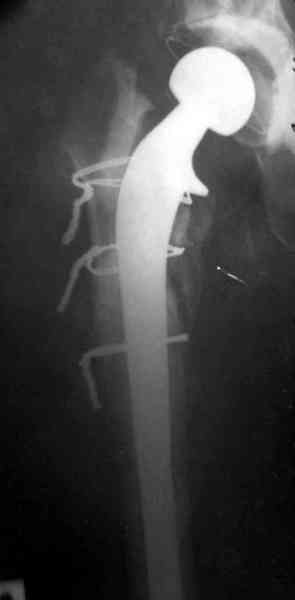

Судя по всему, произошел раскол наружной стенки бедра и ножка находится вне костного канала. В таком случае

решение одно - удаление ножки и установка новой в расчете на дистальную фиксацию. Конктреную модель подсказать тяжело из-за низкого качества Р-грамм.

Приглашенный хирург установил ревизионный вариант бедренного компонента без замены ацетабулярного компонента, что осложнилось нагноением и свищами на уровне сустава и средней трети бедра. После двухгодичного безуспешного лечения перевязками и антибиотиками больная обратилась к нам на консультацию.

Повторная операция по удалению тотального протеза с irrigation&debridment, канал после очистки цемента обильно промыт и рассверлен римером.